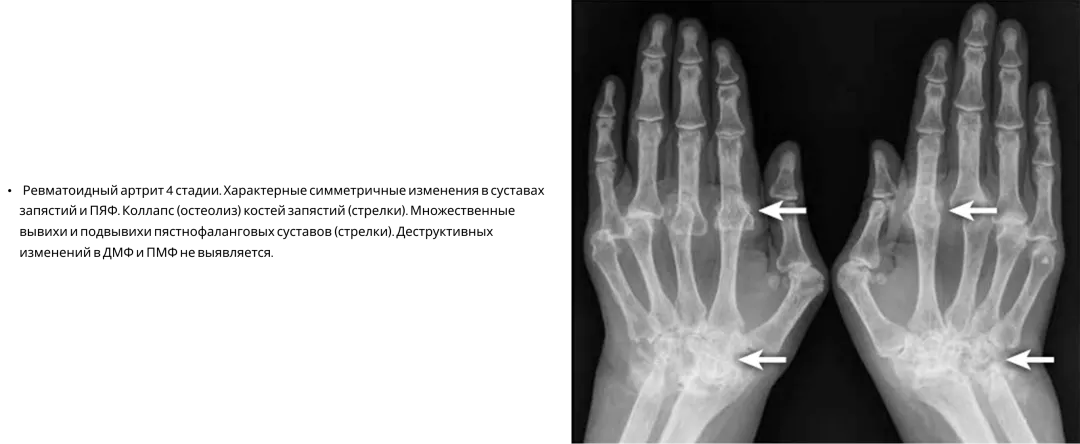

Ревматоидный артрит17

На практике ПсА часто путают с ревматоидным артритом, поскольку при обоих заболеваниях могут поражаться мелкие суставы кистей, характерны костные эрозии. В то же время для РА помимо характерных клинических симптомов есть ряд рентгенологических признаков7.

Image

Frame 24061577 (2).png